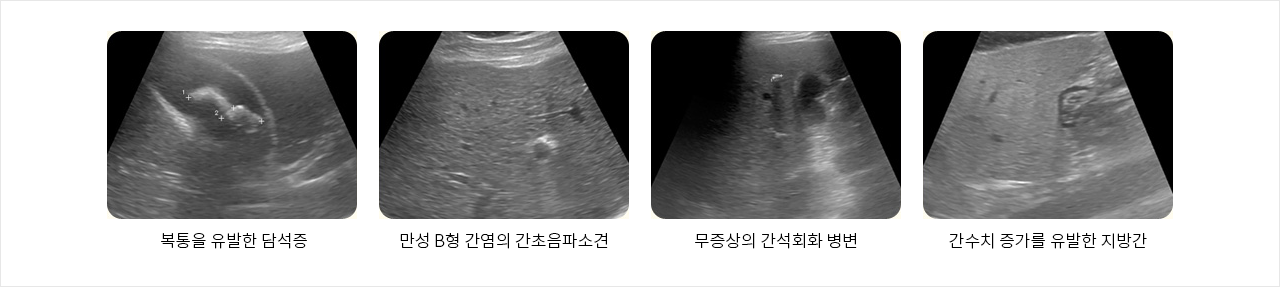

- 복통을 유발한 담석증

- 만성 B형 간염의 간초음파소견

- 무증상의 간석회화 병변

- 간수치 증가를 유발한 지방간